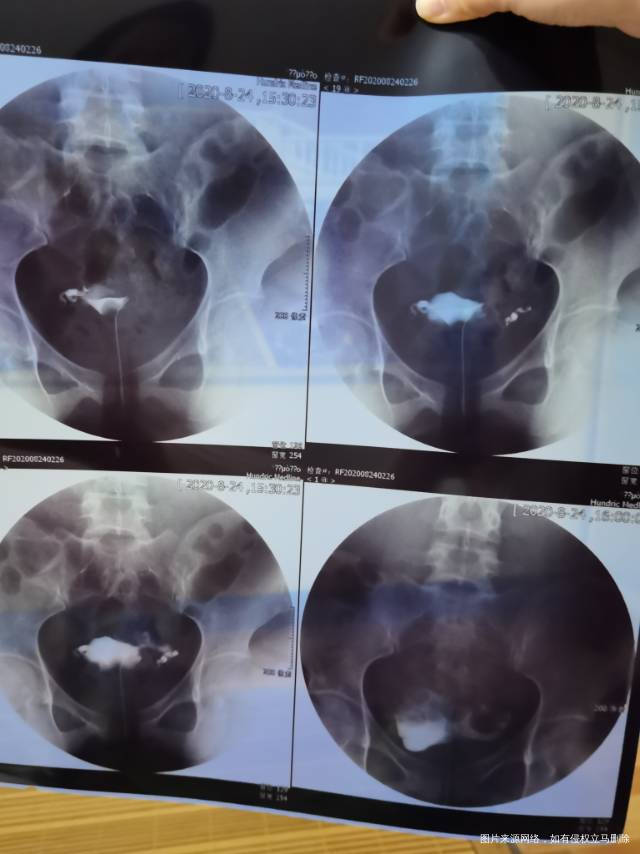

您好,最近做了甲状腺 性激素六项 卵巢功能都正常 之前也连续去医院做排卵检测三个月以上一直也没怀 今天去做了输卵管造影,结果去图片。医生说没问题是通畅的。但报告单写的是右侧输卵管迂曲走形欠佳,这个是什么意思呀。左侧输卵管走形向上,是说左侧没有问题吗?然后延时20分钟后,盆腔内可见造影剂,弥散不佳是什么意思呢。求解答谢谢

不要担心,上面描述都是造影过程中,但结果是双侧输卵管通畅的,所以不要纠结,继续试孕就可以的,一年内怀孕是正常的。可以继续做彩超监测卵泡,指导同房怀孕。也可以排卵期增加同房次数,提高怀孕机率。放松心情有利于怀孕的。

您好,输卵管是好的,建议检查丈夫精液促排卵治疗。